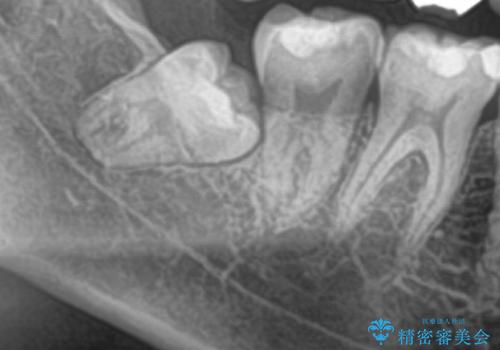

- 当院でセラミック治療を行い、その後に親知らずを抜きたいとのことで来院された患者様です。

CTで神経の位置などを確認し、抜歯術を行いました。

一週間後に抜糸を行いました。